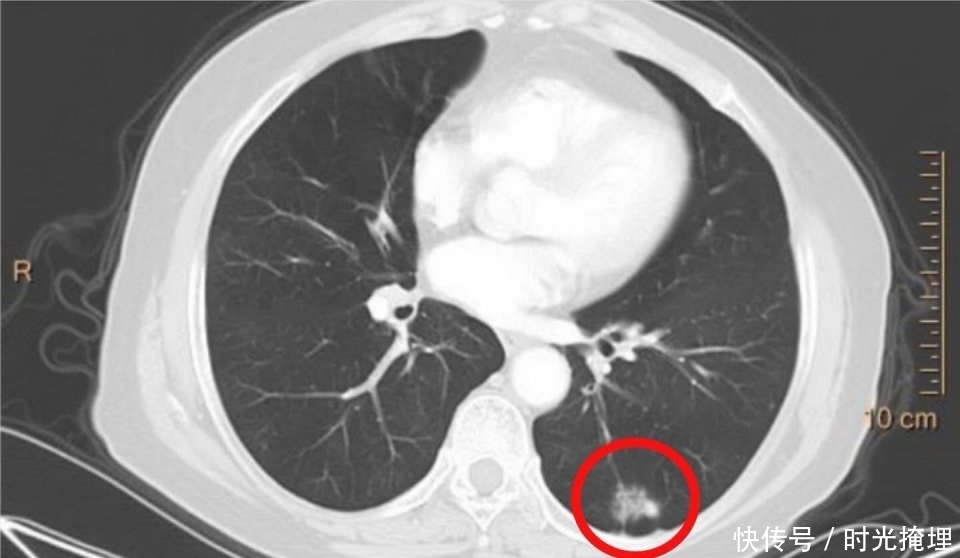

文章插图

这回实在不敢再留了。

手术切除,证实为浸润性肺腺癌。

这个病人没有做任何治疗,前后历时10年半,名副其实的“懒癌”。